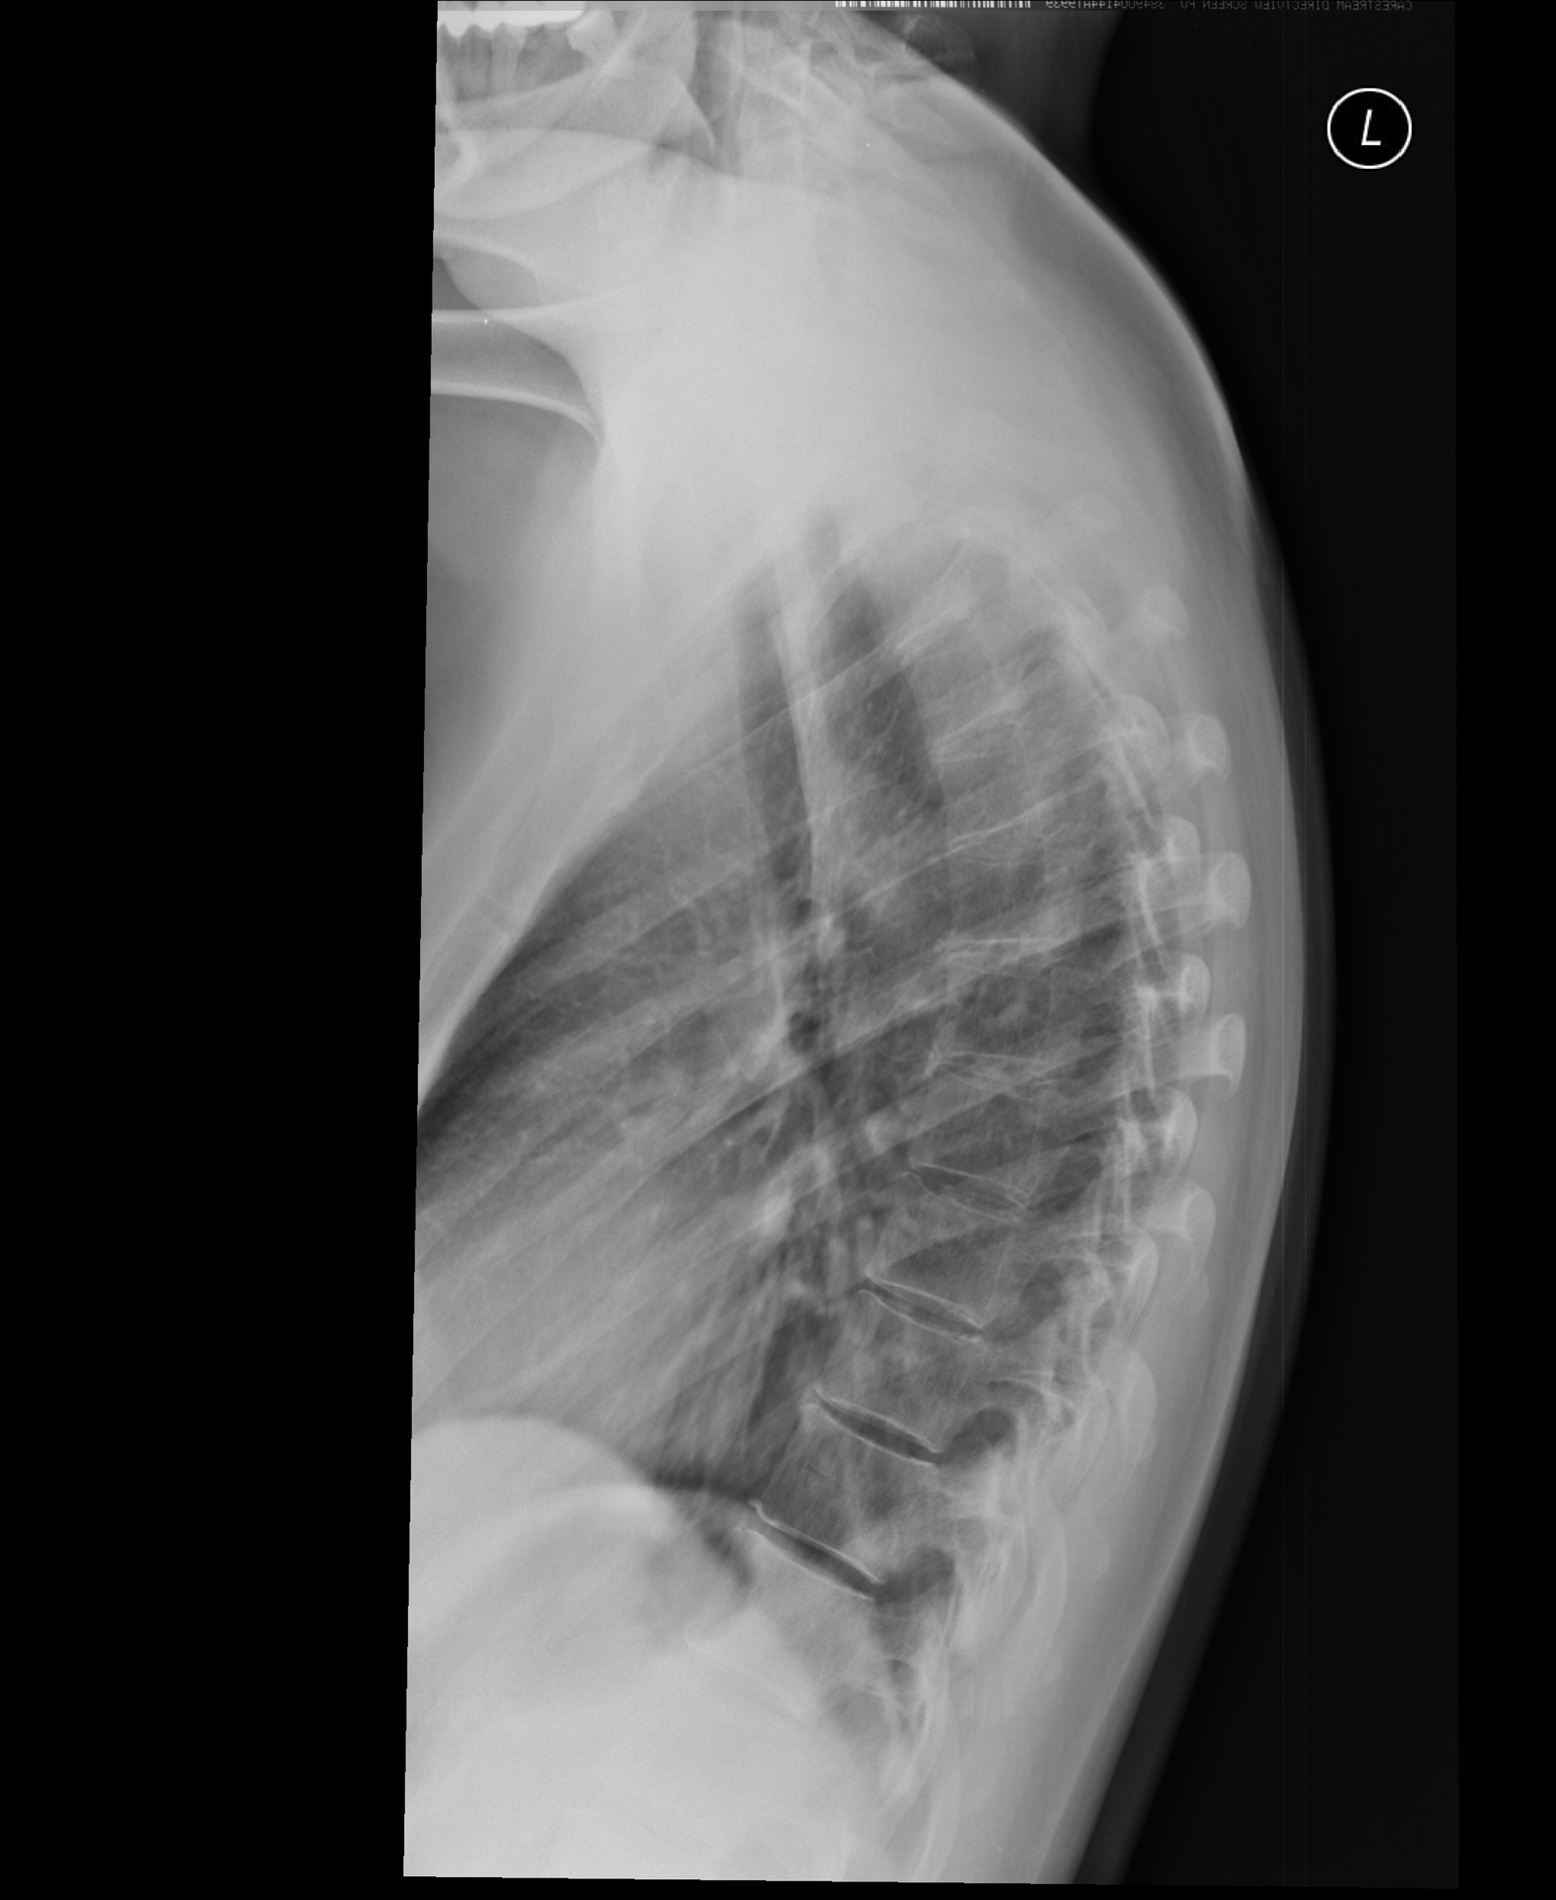

Подтвердить диагноз может травматолог-ортопед, для этого врач оценивает характерные симптомы и проводит обследование. Для определения угла искривления требуется рентгенография позвоночника в двух проекциях. Оценить состояние костей, мышц, спинномозговых нервов, межпозвонковых дисков можно с помощью компьютерной и магнитно-резонансной томографии.